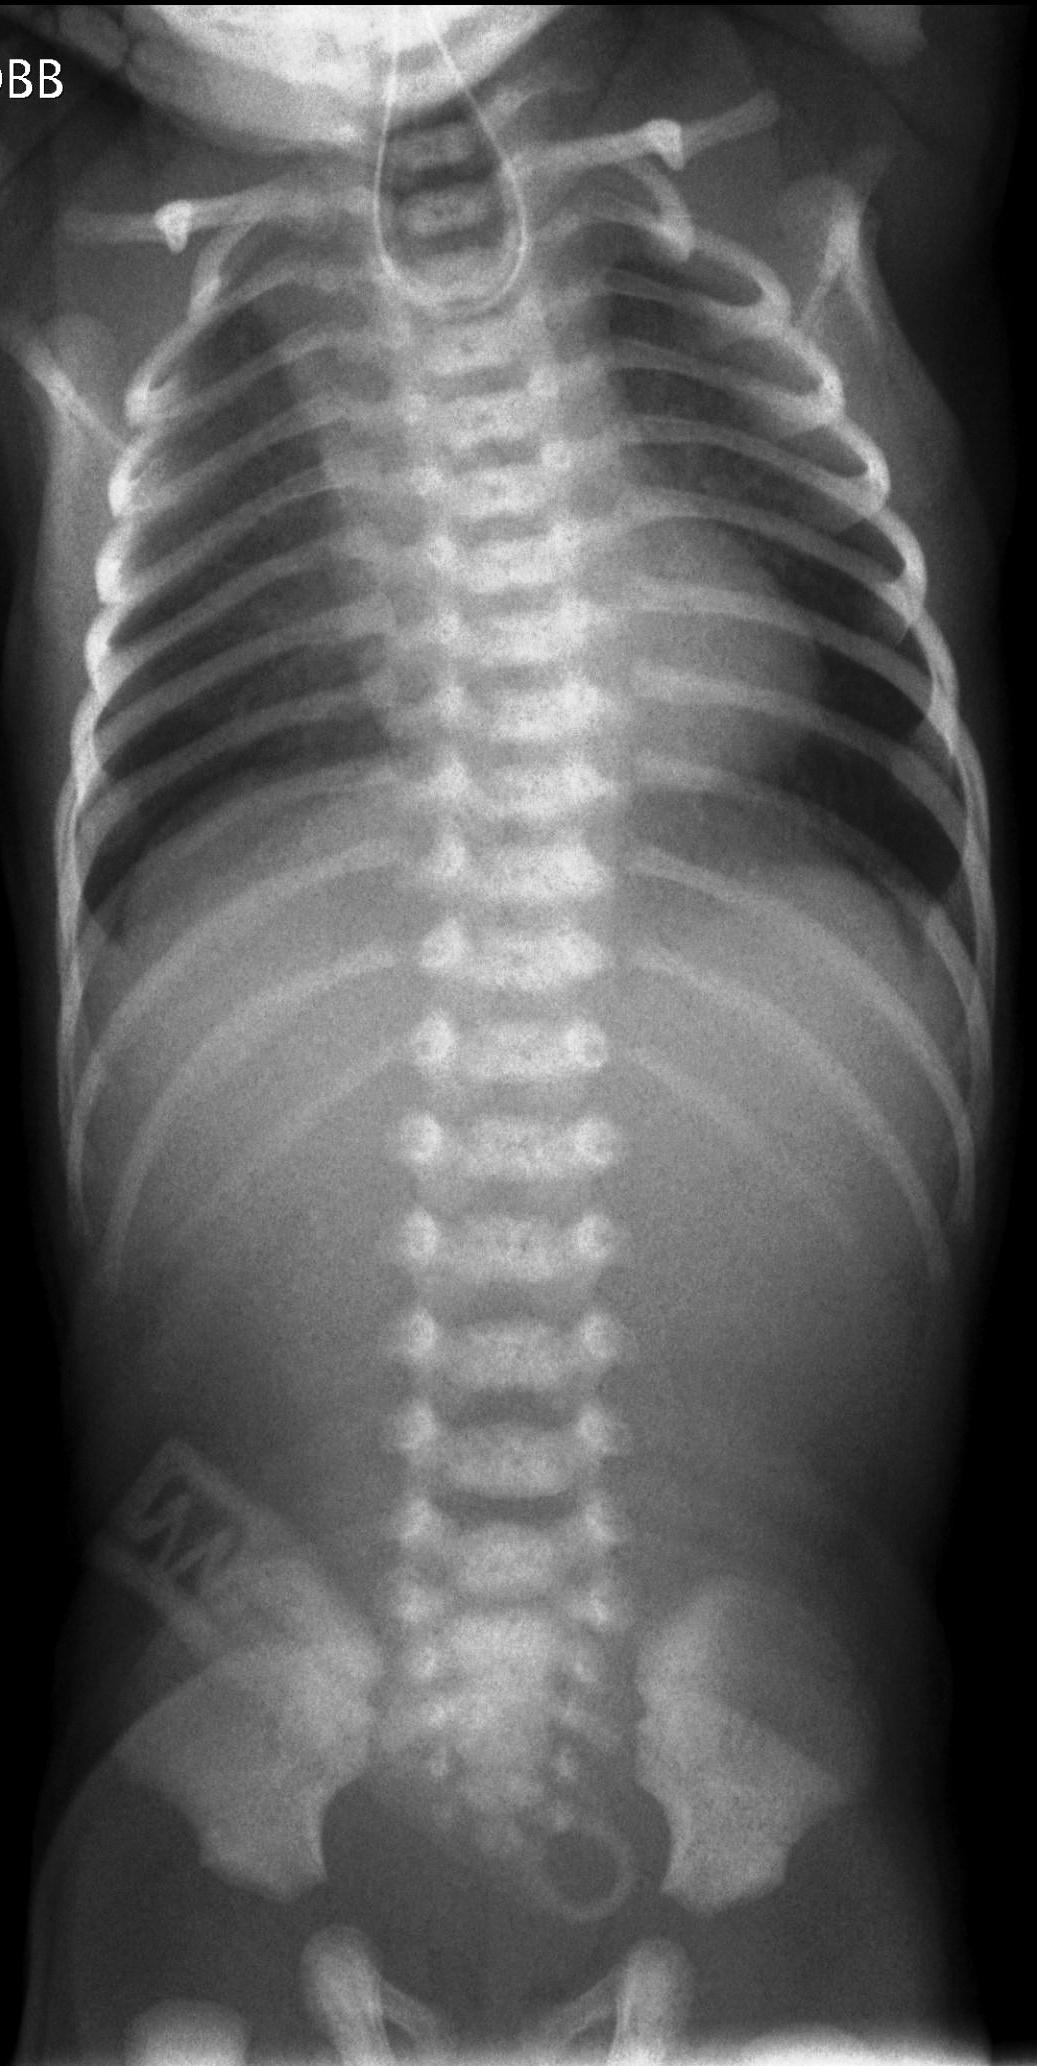

Die Grundlagen Der Padiatrischen Radiologie

Aufnahmen des knöchernen Thorax in mindestens 2 Ebenen. Bei uns in der Klinik ist es langsam zur Gewohnheit geworden Röntgen Thorax in einer Ebene anzufordern obwohl die Patienten nicht im Bett liegen. Hierbei handelt es sich um zwei Aufnahmen die aus verschiedenen Richtungen Ebenen gemacht werden. Ein Röntgen-Thorax gehört für viele medizinische Prozeduren zB. Aufnahmen seiner Teile in mindestens zwei Ebenen Abrechnungsbestimmung. Das sehen wir gleich. Große Bullae rechts Thorax-CT Pleurosis calcarea rechts Thorax pa Pleurosis calcarea links. Aufnahmen des knöchernen Thorax in mindestens 2 Ebenen. Dies ist ein unauffälliger Normalbefund einer Röntgen-Thorax-Aufnahme.

Normalbefund und krankheitstypischer Befund. Sollten Röntgenaufnahmen des Thorax wenn möglich immer in posterior-anterior Strahlengang erfolgen da das Herz ansonsten zu groß dargestellt wird. Normalbefund und krankheitstypischer Befund. Aufnahmen seiner Teile in mindestens zwei Ebenen Abrechnungsbestimmung. Weitere Indikationsstellungen siehe Leitlinien für die Überweisung zur Durchführung von bildgebenden. 3543 FFA mindestens 150m - 250m Fernaufnahme. 5004 Panoramaschichtaufnahme der Kiefer.